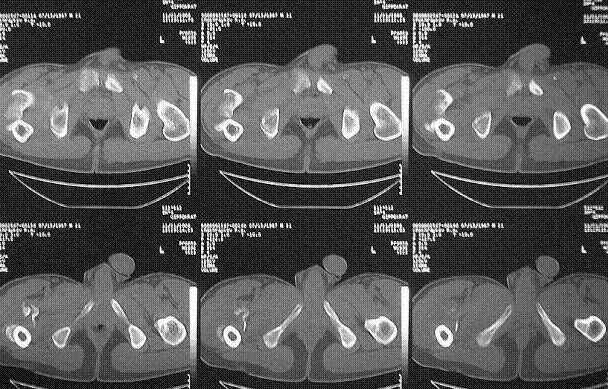

Если судить по снимкам, то укорочение кажеться не критическим, но обьективно и на 3D - укорочение на 6-7 см.

Думаю сделать так: под адекватной анестезией на тракционном столе попробую максимально низвести бедро. Если получится, рентгенконтроль/оценка ситуации и Blade Plate с костной пластикой (помню предостережение Александра Николаевича о возможной варусно-антекурвационной установке центрального отломка и трудности в использовании Гамма-гвоздя). Если останется укорочение на 3-4 см придется на короткое время (2-2,5 недели) наложить стержневой аппарат "бедро-бедро" и дробно, но форсированно, ориентируясь на ощущения больного и поведение дистальных отделов конечности адаптировать отломки (больной на это период останется в стационаре). Если же появятся первые признаки воспаления мягких тканей в области проксимальных стержней, аппарат снимаю, перевожу на скелетное вытяжение и готовлю больного ко второму этапу.